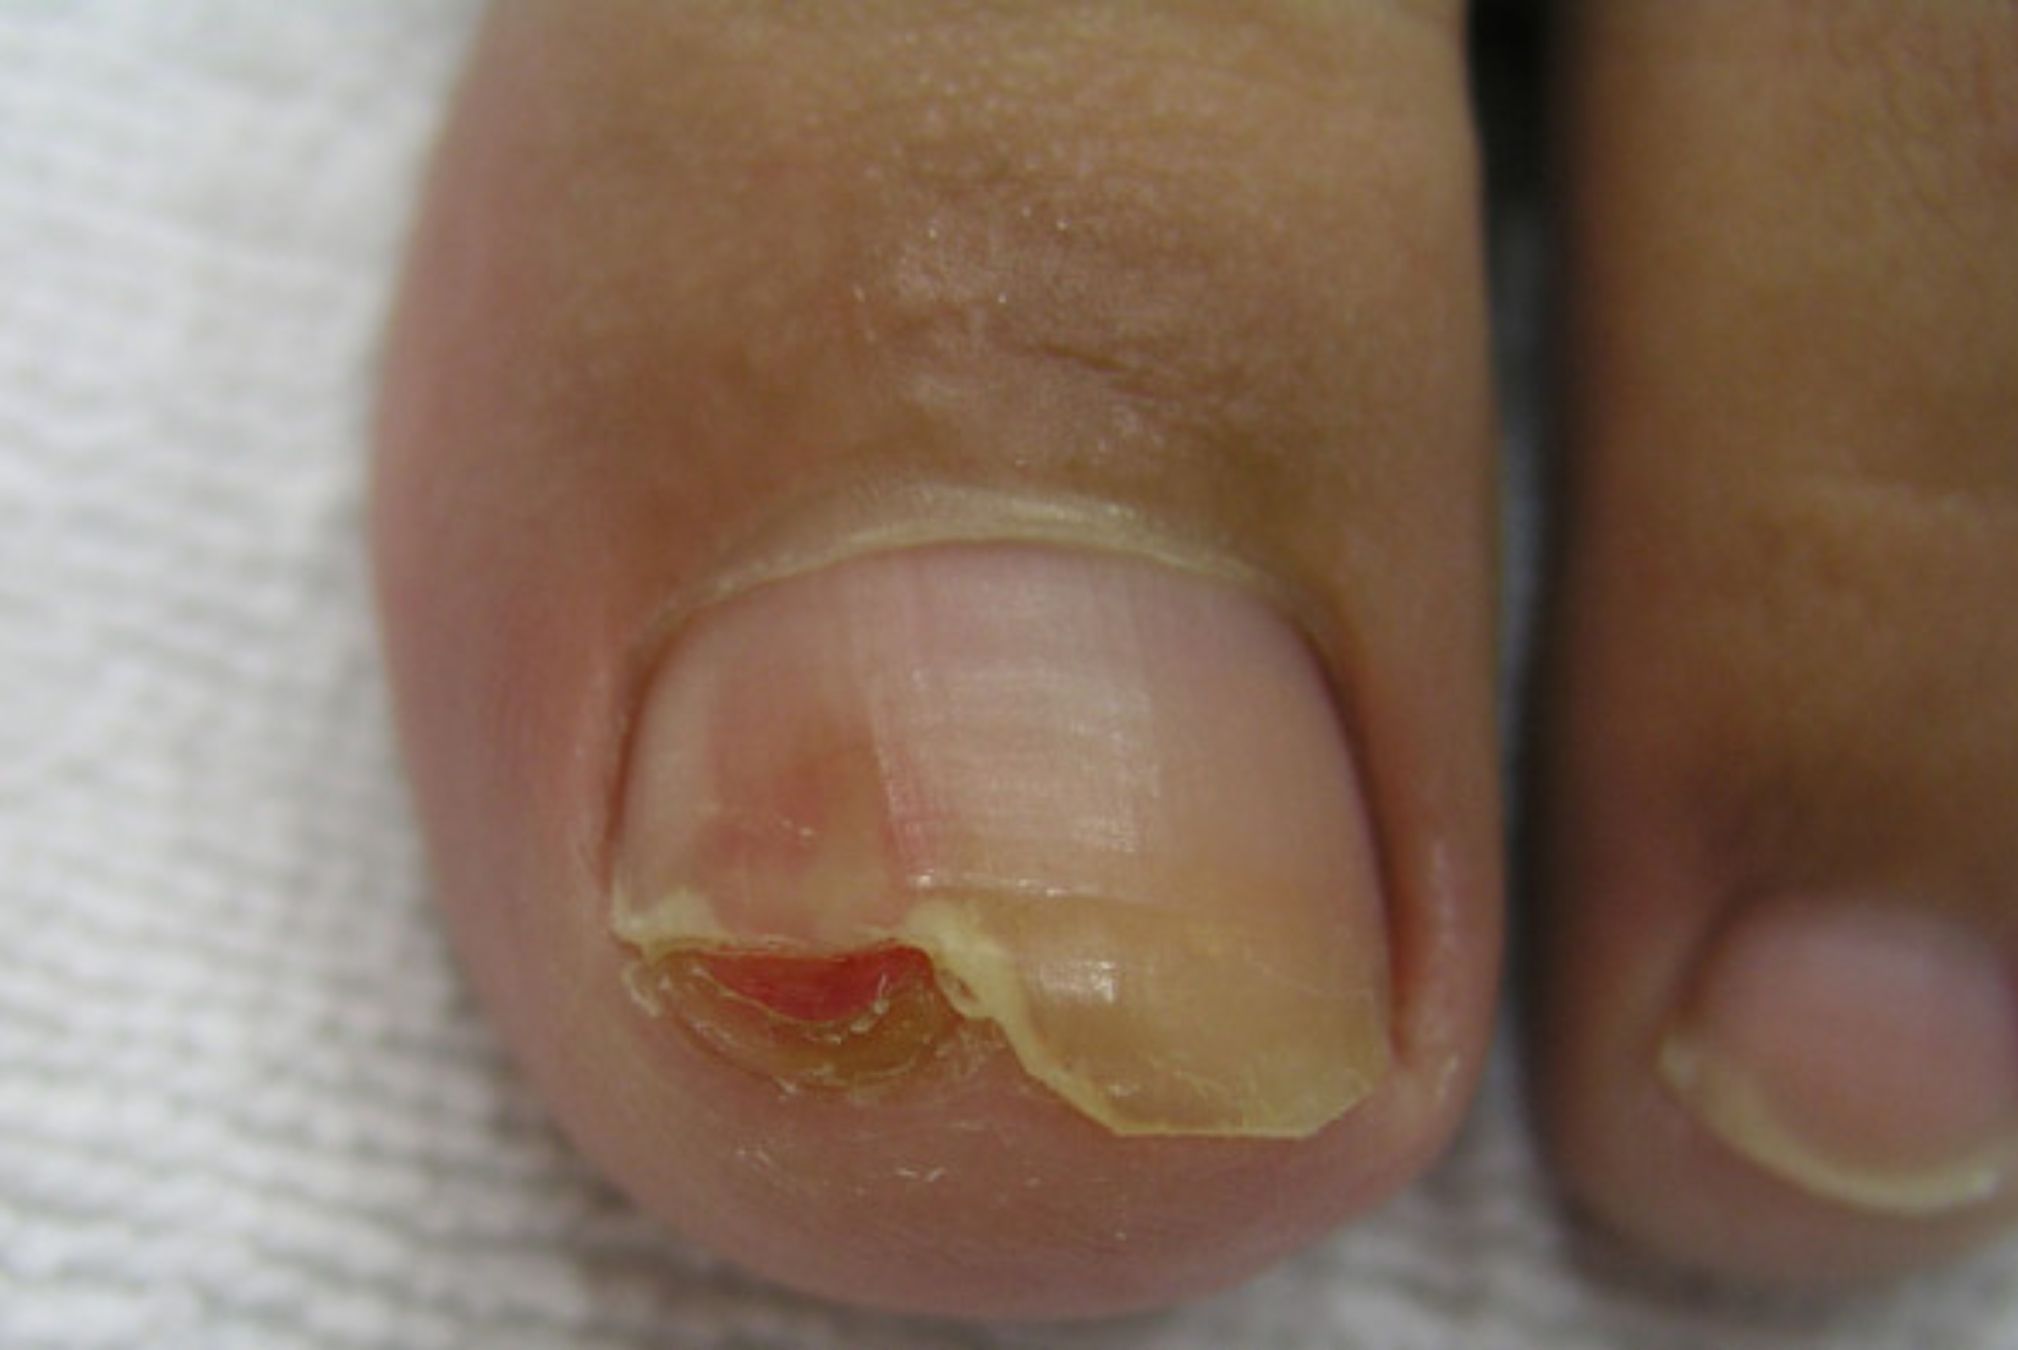

Ποια είναι η εικόνα στην ονυχομυκητίαση;

Η εικόνα ενός νυχιού που πάσχει ποικίλει από αλλαγή του χρώματος σε κάποιο σημείο (ονυχοδυσχρωμία) από το φυσιολογικό ροζ σε κίτρινο, καφέ ή πράσινο. Μερικές φορές το νύχι παχαίνει, ανασηκώνεται και ξεκολλάει από το «κρεβάτι» του στο δάκτυλο ή λεπταίνει. Σε προχωρημένες καταστάσεις το νύχι δείχνει κατεστραμμένο.